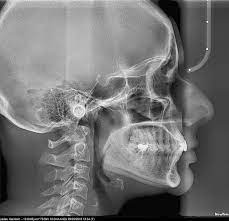

Telerendgen, poznat i kao TR snimak, predstavlja vrstu rendgenskog snimanja koja se koristi u stomatologiji i ortodonciji za analizu kraniofacijalne strukture. Ova tehnika omogućava procenu odnosa zuba, vilica i lica, pružajući klinički značajne informacije za dijagnozu i planiranje ortodontske terapije.

Telerendgen je lateralni (bočni) rendgenski snimak glave koji prikazuje kosti lica, zube i okolne strukture u profilu. Ovaj snimak omogućava ortodontima da prouče položaj i odnose između gornje i donje vilice, kao i položaj zuba u odnosu na ostatak kraniofacijalnog skeleta.

Tokom snimanja, pacijent stoji ili sedi pored rendgenskog aparata, a njegova glava je postavljena u specifičan položaj. Telerendgen koristi držač glave kako bi se osiguralo da je pacijentova glava stabilna i u pravom položaju tokom snimanja. Proces je brz i bezbolan, a snimak se koristi za detaljnu analizu u specijalizovanom softveru.